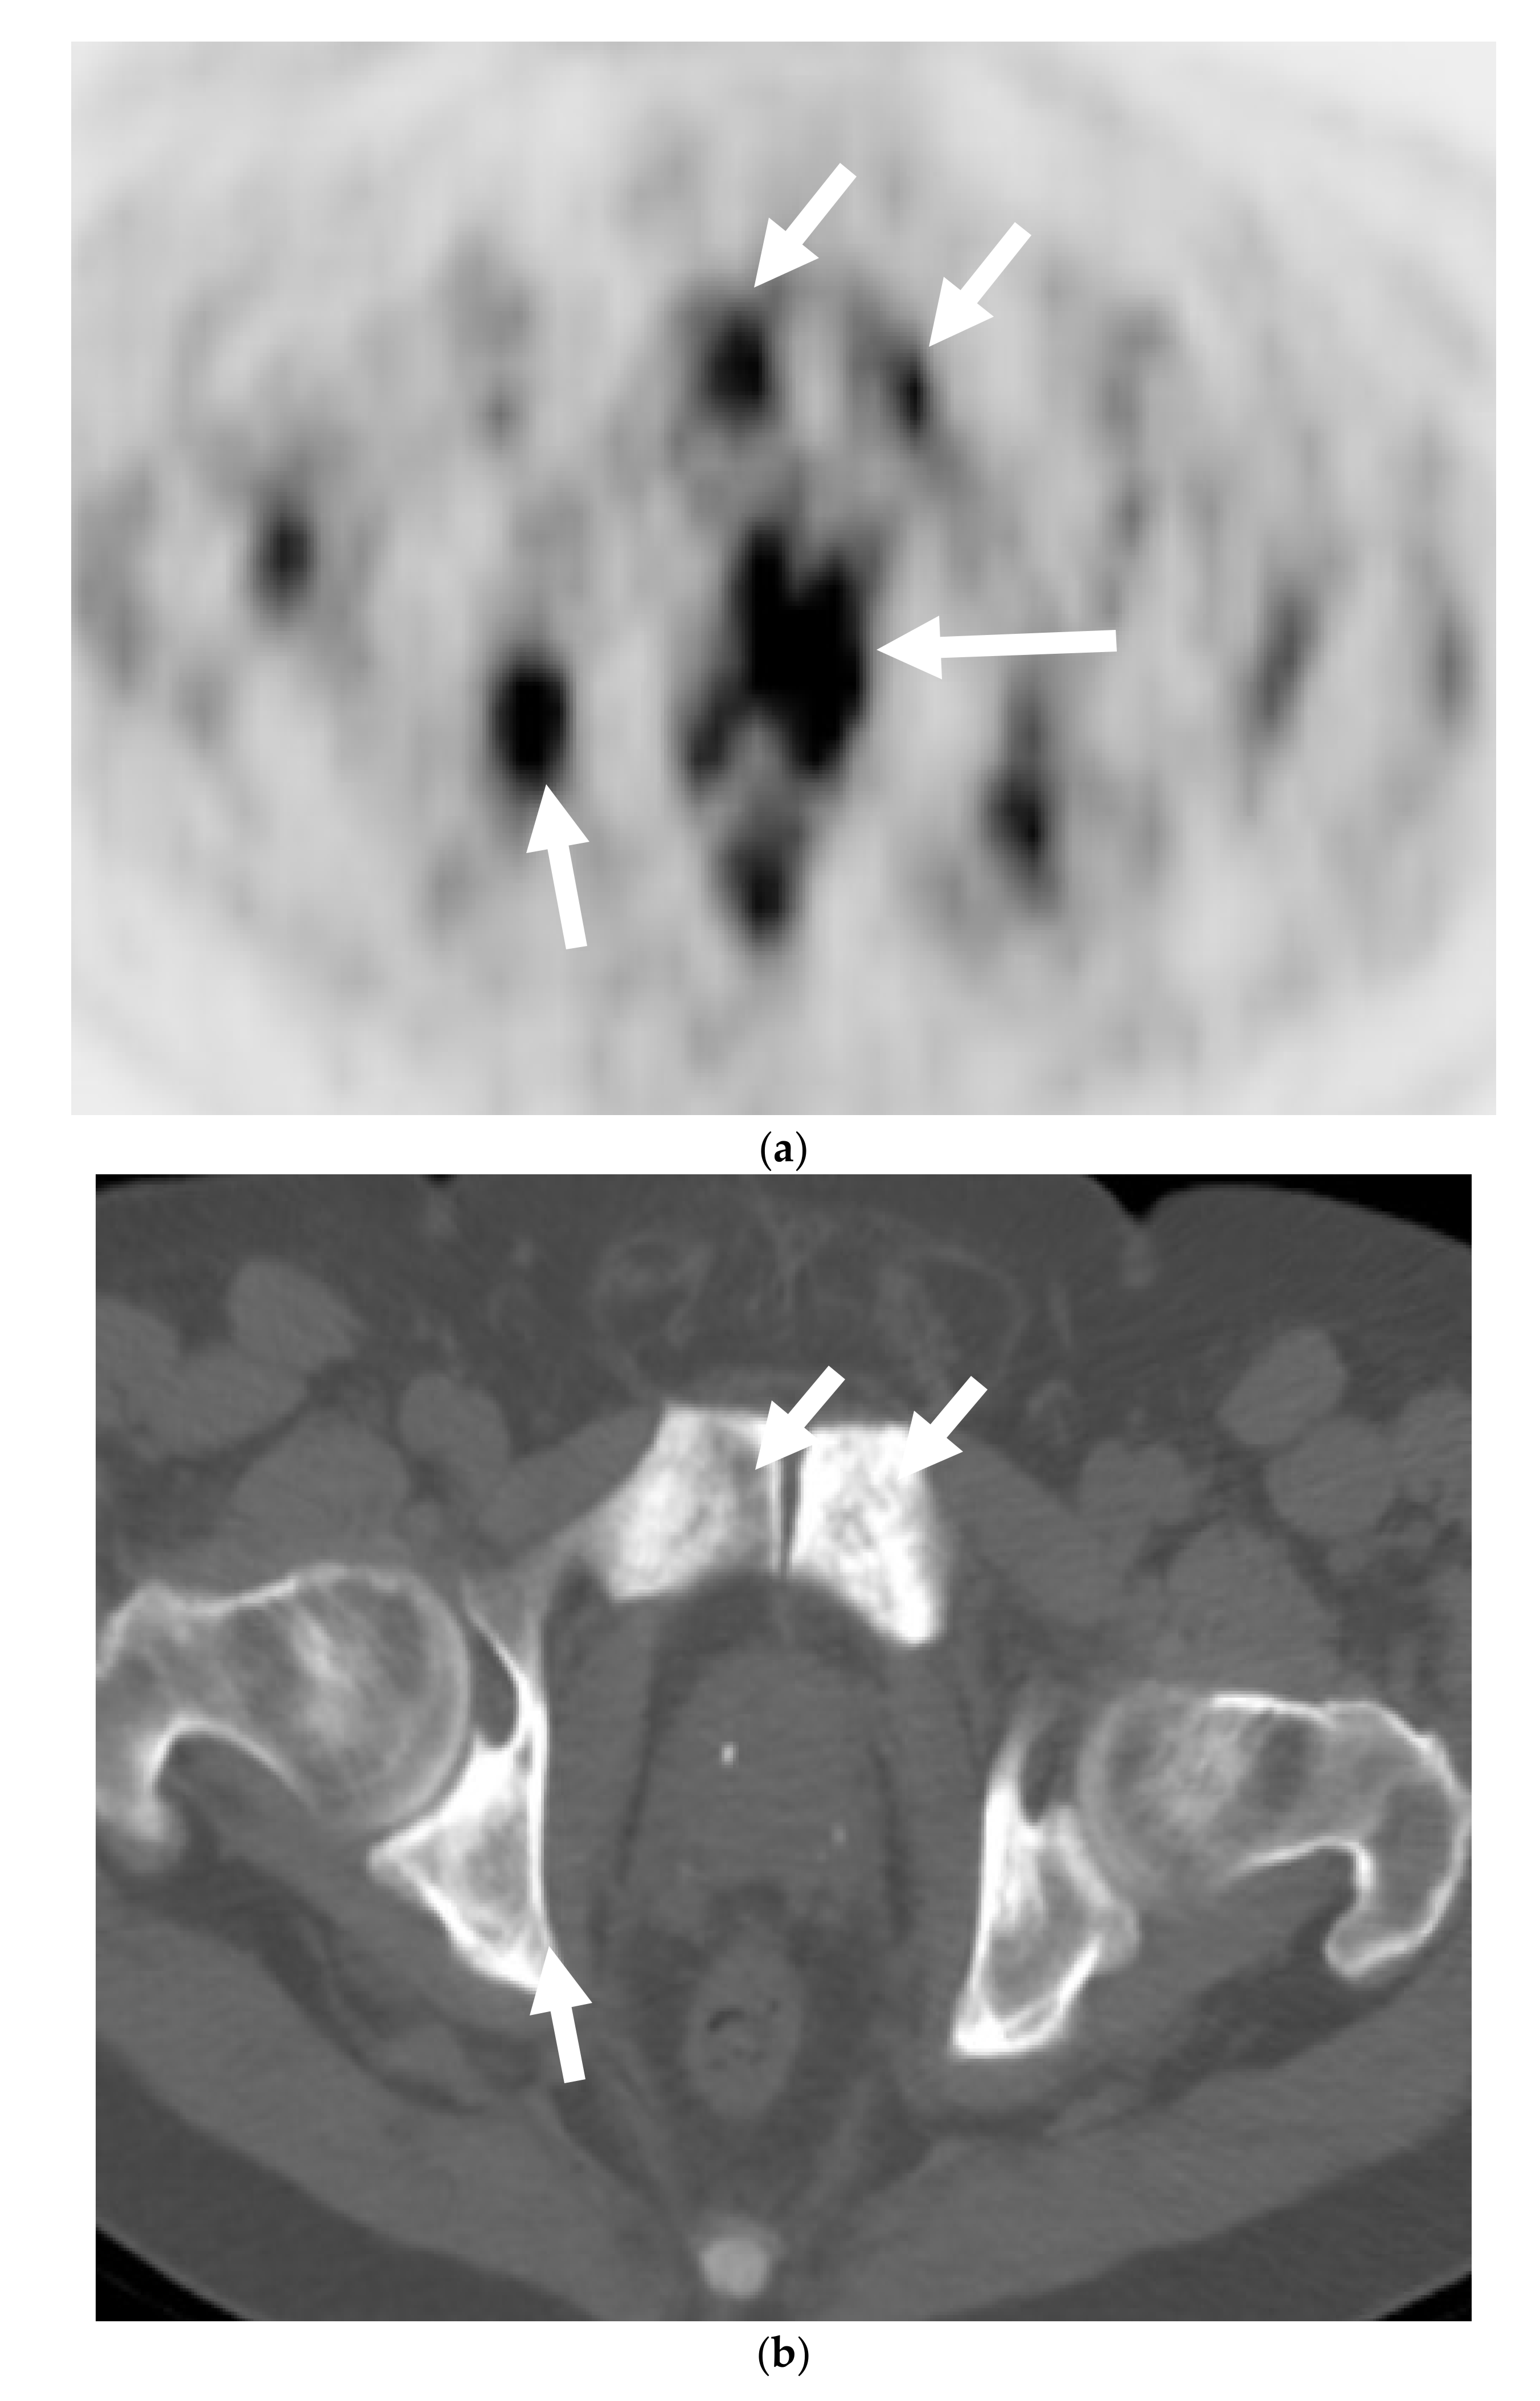

Figure 2. A 68-year-old man with palpable prostatic mass on rectal examination. Serum PSA was 0.3 ng/mL. Axial FDG-PET (a) and corresponding anatomic CT (b) of the PET-CT shows intensely hypermetabolic prostatic mass (long arrow) and pelvic bone metastases (short arrows). Axial lung window reformat of the CT chest (c) shows numerous small pulmonary nodules suspicious for metastases (arrows). Prostate biopsy showed high-grade carcinoma with neuroendocrine differentiation.- -

Most of the literature states that MDCT typically plays no role in the detection of PNEC and is not recommended for diagnosis. The only role of CT is for nodal staging, but it is also limited for this purpose, due to its inability to detect neoplastic architectural changes within less than 10 mm normal-sized lymph nodes (LNs) [30,31]. MDCT plays an important role in M staging for detection and restaging for bone and lung metastases in these cases (Figure 2 and Figure 3).

FDG is a glucose analog and its uptake reflects the tissue glucose metabolism. Due to increased uptake in neoplasms, resulting from the increased metabolic activity of the tumor cells, it is the mainstay of molecular imaging and the most commonly used PET tracer to evaluate tumors [47,48]. It has a limited value when it comes to prostate cancer as a result of low glucose metabolism and the use of non-glucose metabolic pathways, e.g., fructose and fatty acid metabolism in the tumor [49,50]. However, Spratt et al. demonstrated that 18FDG PET has clinical utility in the metastatic evaluation of NEPC (Figure 2) and this may be due to high glucose metabolism of the usually high-grade neuroendocrine cancers seen in prostate. FDG PET findings can also serve as prognostic marker in cases of metastatic NEPC. When stratified by the median survival from NEPC diagnosis, patients who survived <2.2 versus ≥2.2 years, had more PET avid bone and soft tissue lesions and higher average SUVmax of bone and soft tissue lesions [51,52]. Some low-grade neuroendocrine tumors may not be intensely FDG-avid and rather may be more intensely avid on 68 Gallium DOTATATE PET, as shown with gastroenteropancreatic neuroendocrine neoplasms [53].

There is no core difference in staging between prostatic adenocarcinoma and NEPCs. The TNM staging system, developed by the American Joint Committee on Cancer (AJCC), is the most commonly used staging method to assess the tumor status (T), lymph nodes (N), and metastasis (M) [70]. Unlike prostatic adenocarcinoma, clinical tumor stage 1 is uncommonly seen in cases with NEPC and they usually present with higher stages, with more visceral and nodal metastases with predominantly lytic bone lesions. Hence, NEPC is clinically suspected when a prostate cancer is seen with absent or a low/moderate rise in PSA, presents at advanced stage, or has a predominance of visceral and/or bone metastatic disease (Figure 2). In addition, NEPC is also suspected when the prostate cancer becomes unresponsive to ADT with rapid disease worsening (Figure 3 and Figure 4) [68,69]. Paraneoplastic syndrome is also a potential distinguishing feature for NEPCs, especially SCNC, with Cushing’s syndrome being the most common manifestation [71,72]. Currently, the reference standard for the diagnosis of NEPCs is pathologic examination showing the above microscopic features, plus the presence of neuroendocrine IHC markers, e.g., NSE, SYN, and CgA [16,73].